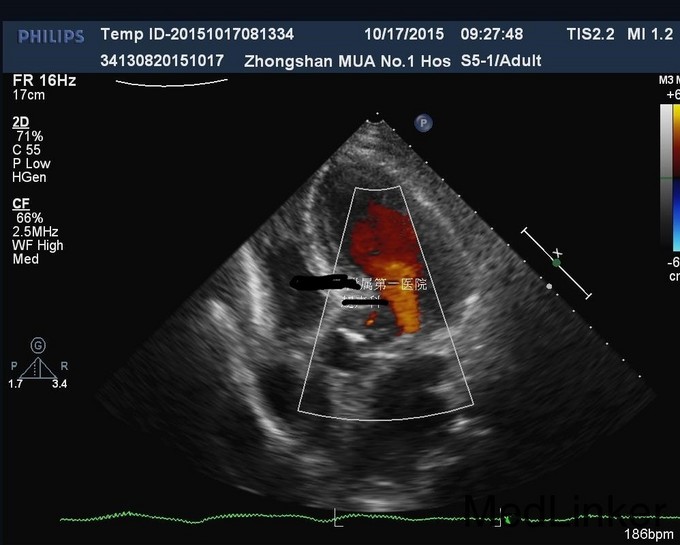

老年男性患者,1年前因腹部膨隆查腹部B超发现肝囊肿,最大直径约21cm,于香港门诊治疗,建议密切随访。近期诉腹胀较前加重,超声示囊肿较前增大。患者无腹痛,无返酸,无发热、黄疸,无呕血,无黑便。既往高血压病20余年,服药控制良好。现为进一步手术治疗入院。

查体: 皮肤黏膜无黄染及苍白,腹部膨隆,腹肌软,未触及肝脏肋下缘,无肝震颤。 辅查: 1.腹部CT:1.肝内多发囊肿,其中右叶可见巨大囊肿。 2.胆囊结石。 3.右肾小囊肿;左肾小结石。 2.术后病检: 1(胆囊)送检5.5x2x1cm组织一块,内见结石。镜下:慢性胆囊炎,胆囊结石。2(囊壁)送检直径6cm囊壁样组织一块,囊壁厚0.1cm。 镜下:送检纤维囊壁样组织,部分囊壁披覆单层上皮,局部囊壁可见少量肝组织,病变符合肝囊肿。

诊断:1.肝内多发囊肿 2.胆囊结石 治疗:完善术前准备,未见明显禁忌,且患者强烈要求美观、微创,遂决定在气管内麻下行机器人辅助下肝囊肿开窗引流+囊肿切除+胆囊切除术。手术过程顺利,术中病情平稳。术后安返病房,给予禁食、心电监护、吸氧、肠外营养、止血等对症支持治疗。